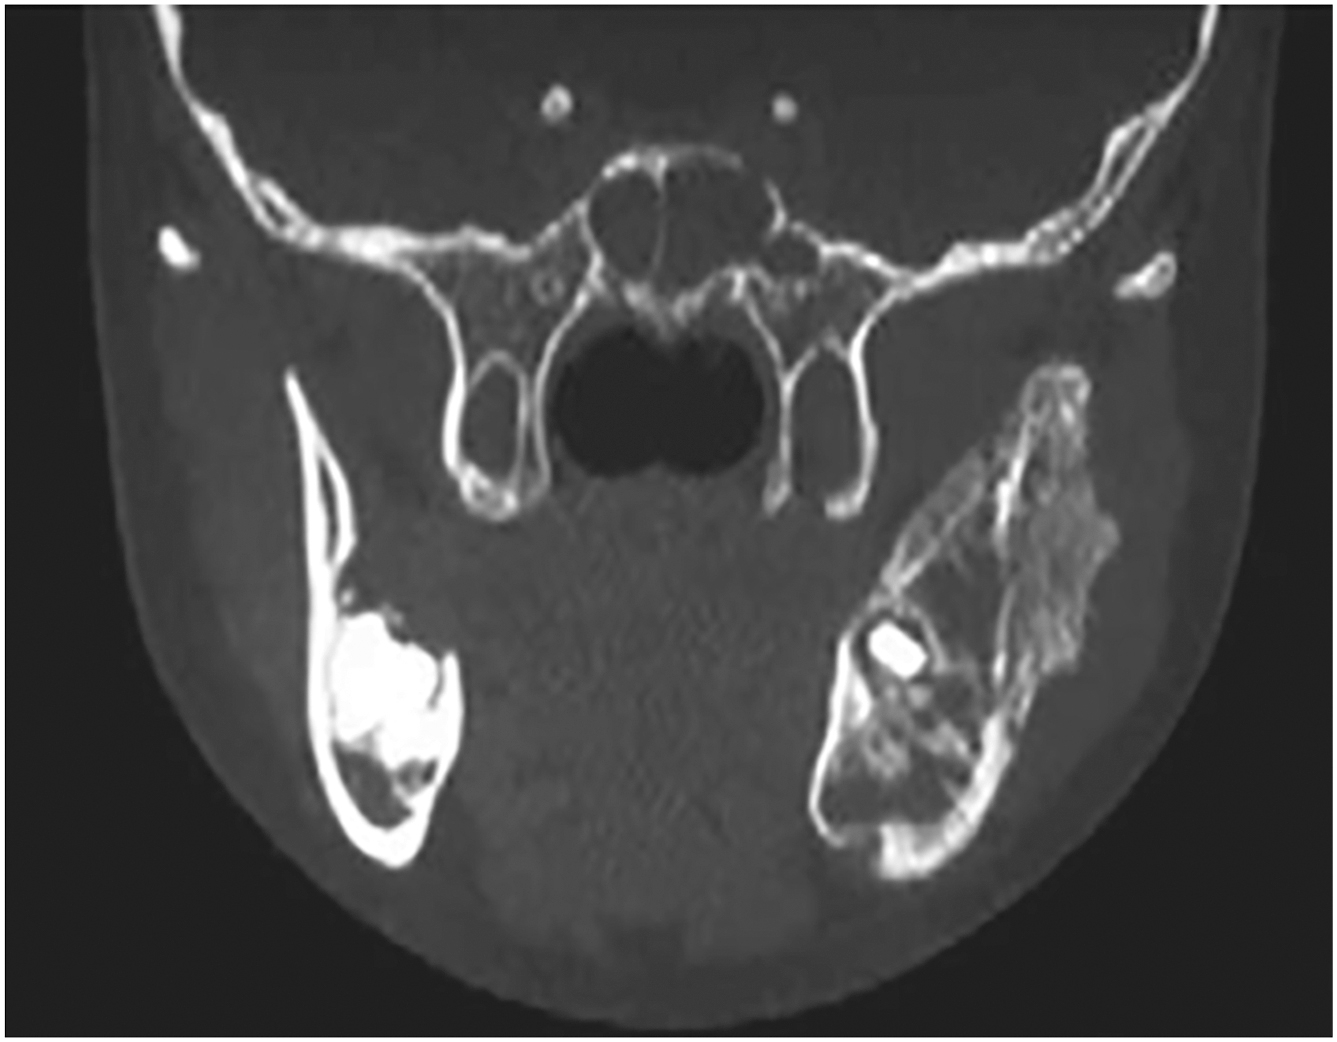

We present two cases to highlight the potential for excellent aesthetic and functional outcomes in pediatric patients undergoing free tissue transfer. Case 1. A young boy underwent fibula free flap reconstruction following Isolated neuroblastoma ( Fig. 1 ) resection from the mandible via segmental mandibulectomy ( Fig. 2 ). Rib graft was used for condylar head reconstruction and fibula for mandibular bone with temporalis tendon suspension ( Fig. 3 ). 1 year postoperative outcome demonstrates excellent occlusion and mouth opening ( Fig. 4 ). Case 2. A young girl presented with a parapharyngeal space tumor ( Fig. 5 ) found to be rhabdomyosarcoma. She underwent a lip split mandibulotomy approach with resection of the parapharyngeal space rhabdomyosarcoma ( Figs. 6 and 7 ). A radial forearm free flap was used to cover the pharyngeal space defect ( Fig. 8 ). Post-operative 1 year outcome with excellent aesthetic outcome and mandibular opening ( Fig. 9 ).